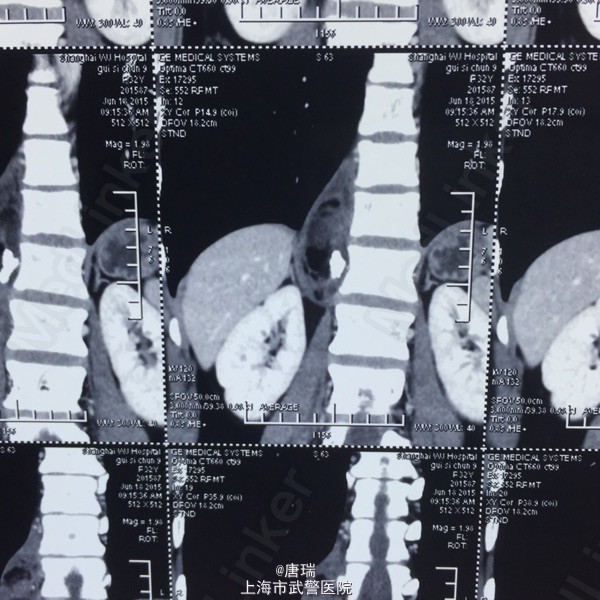

腹膜后占位,错构瘤与畸胎瘤的鉴别

畸胎瘤

体检发现脊柱旁腹膜后占位。